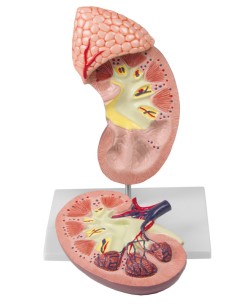

Dal cranio in 22 parti con incastri magnetici ai modelli di colonna vertebrale, da quelli di articolazioni a quelli di cuore, ogni pezzo della nostra collezione è progettato per un’immersione totale nello studio dell’anatomia umana. I nostri modelli, realizzati tramite scansioni di ossa vere, garantiscono un’esperienza tattile autentica e una fedeltà di peso quasi identica agli originali.

Essenziali per studenti e professionisti, i nostri modelli anatomici sono strumenti didattici che permettono di osservare le strutture anatomiche con precisione, eliminando la necessità di dissezioni o studi invasivi. Sono inoltre utili per spiegare ai pazienti le patologie, rendendo la comunicazione più efficace e risparmiando tempo prezioso.